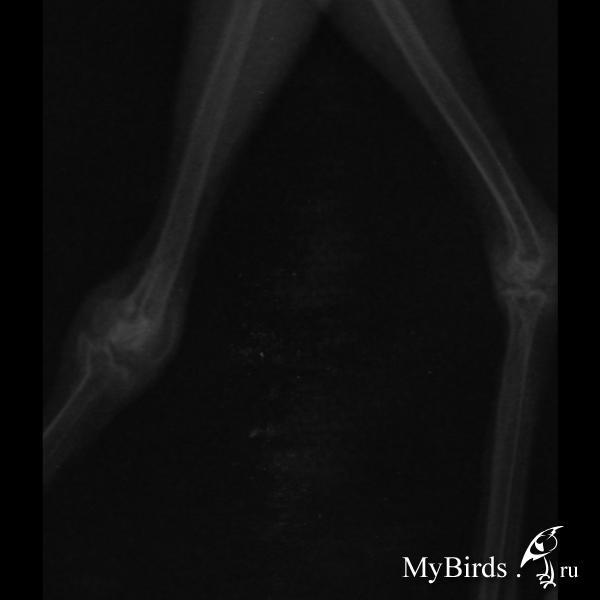

Сороку подобрали 22 июня. Отбили у котов, которые пытались ее съесть. Первое время птенец прихрамывал и беспокоило крыло. Примерно через неделю лапка и крыло его перестали тревожить. Но вот уже немногим больше недели как он начал все сильнее и сильнее хромать, как раз после того как стал проводить в квартире все больше и больше времени, почти весь день, т.е. существенно возросла нагрузка на лапку. Сустав (скакательный? колено? не знаю как правильно) увеличился, пальчики стали не такие цепкие (заметна большая разница со здоровой лапкой) и лапка искривлена в суставе.

Вчера ходили в клинику, рентген показал старый перелом и уплотнение в колене. Прописали компрессы из траумеля и гепариновой мази (1:1). Так же ограничить движение. На следующей неделе еще раз попросили привезти птичку, т.к. травматолог в отпуске.

post-62939-1440925762_thumb.jpg